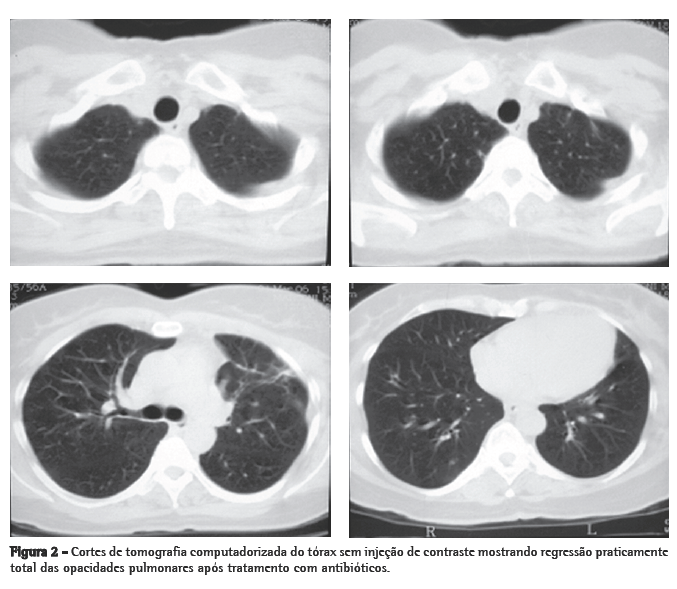

Mulher de 56 anos, branca, procurou o serviço de emergência devido à tumoração em região cervical à direita, dolorosa, há 5 dias. Apresentava tosse seca e febre alta há 3 dias. Negava tabagismo. Era hipertensa e diabética e havia tido um infarto do miocárdio há 3 anos. Na admissão, a paciente apresentava-se desidratada, afebril (temperatura axilar, 36,7°C), eupnéica, com tumoração cervical dolorosa à direita. Os exames laboratoriais revelaram velocidade de hemossedimentação aumentada (92 mm). A ecografia cervical mostrou trombose em VJI direita, sendo iniciada anticoagulação no quarto dia de internação. A radiografia de tórax demonstrou pelo menos dois nódulos no pulmão esquerdo, um aparentemente escavado e outro com 18 mm de diâmetro na base, além de lesão irregular com 25 mm de diâmetro no lobo superior direito. Foi realizado ecocardiograma transesofágico para descartar a hipótese de endocardite, o qual não demonstrou presença de vegetações. Devido à hipótese de pneumonia, foi iniciado tratamento empírico com 500 mg de cefuroxima, via oral, a cada 12 h. A tomografia de tórax revelou múltiplas opacidades bilaterais, de aspecto sugestivo de implante metastático (Figura 1). Prosseguindo a investigação, a paciente foi submetida à broncoscopia flexível, cujos achados endoscópicos foram normais. A análise microbiológica do lavado broncoalveolar para pesquisa de bacilo álcool-ácido resistente e fungos, assim como seu estudo citopatológico e culturas, foram negativos. Com a hipótese de neoplasia metastática, a paciente foi submetida à biópsia pulmonar cirúrgica, cujo exame anatomopatológico mostrou inflamação supurativa crônica abscedada em organização em parênquima pulmonar. Frente à hipótese de síndrome de Lemierre devido à trombose jugular associada à embolia séptica pulmonar, a paciente foi questionada sobre a ocorrência de amigdalite no início do quadro. A paciente não recordava, mas a filha lembrou que a mesma havia usado 500 mg de amoxicilina, via oral, a cada 8 h por 10 dias, para tratamento de amigdalite alguns dias antes da internação. Na admissão hospitalar, a paciente recebeu um curso de cefuroxima (750 mg endovenoso a cada 8 horas por 7 dias) concomitante a azitromicina (500 mg via oral por 5 dias),que, por persistência da febre, foi modificado para cefepime (1.000 mg a cada 12 horas por 7 dias).

O envolvimento pulmonar nesta síndrome é extremamente comum (até 97% dos casos). As lesões pulmonares podem se manifestar já no primeiro dia de sepse. Podem ocorrer dor pleurítica intensa com dispnéia e, freqüentemente, hemoptise. Estertores crepitantes localizados e atrito pleural podem ser auscultados. A radiografia de tórax mostra tipicamente múltiplas opacidades bilaterais e pequenos derrames pleurais. É possível detectar-se cavitação já na primeira radiografia. Pode haver rápida progressão das lesões, mesmo na vigência de antibióticos. Empiema desenvolve-se entre 10% a 15% dos casos. Abscesso, pneumotórax e pneumatoceles são descritos. Com administração de contraste, ocorre realce periférico das lesões com áreas centrais de redução da atenuação. O diagnóstico diferencial é com pneumonia (bacteriana aguda, atípica, aspirativa e estafilocócica).(1,2,11-14)